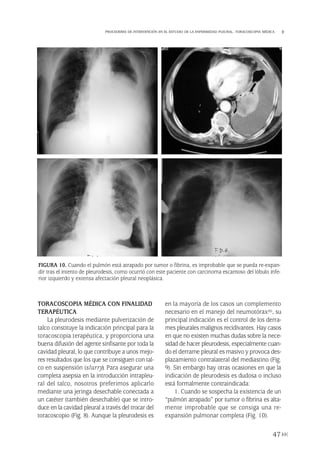

nóstico de linfoma, la citometría de flujo pue-

de establecer el diagnóstico al demostrar una

proliferación celular clonal en el líquido pleu-

ral(84). Por el contrario, los marcadores tumo-